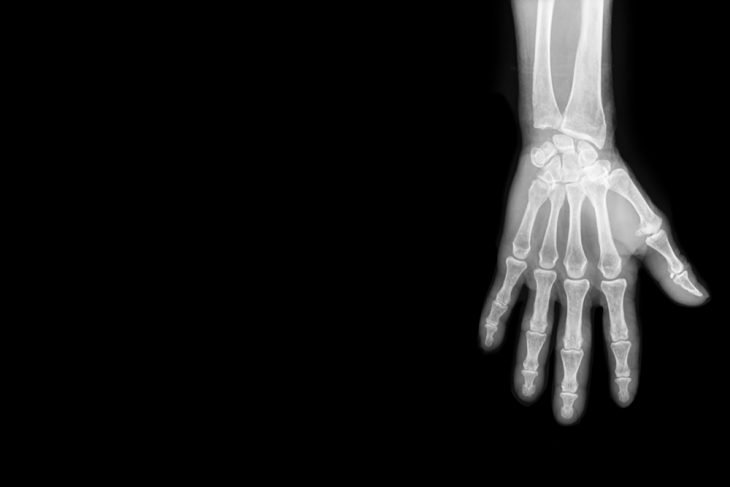

Самостоятельно определить наличие вывиха пальца руки или его перелом невозможно, т. к. точный диагноз может ставиться только на основании данных рентгенологических снимков. Визуально такие повреждения хорошо заметны и проявляются значительным изменением внешнего вида пальца, но с точностью исключить отсутствие повреждений целостности кости может только специалист.

Для выявления вывиха пальца руки врач осматривает больного, уточняет детали травмы и назначает ему проведение рентгенографии, результаты которой позволяют поставить точный диагноз. При появлении подозрений на ущемление сухожилия сгибателя (при травме I пальца) может рекомендоваться выполнение КТ или МРТ сустава.